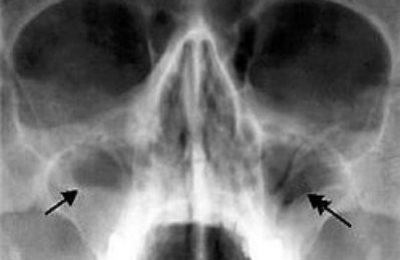

Необходимым условием в диагностике состояния околоносовых пазух, является рентгенологическое сканирование костных носовых перегородок.

Затемнения на рентгеновском снимке, в определенных зонах, дают возможность врачу определить, каким способом лечить хроническое воспаление.